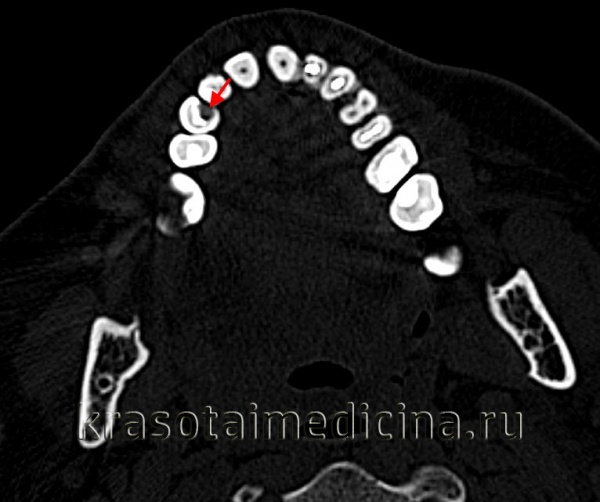

- Рентгенологическое исследование. Пациенту выполняется внутриротовой прицельный снимок одного или двух-трех больных зубов. На нем хорошо визуализируются размеры и глубина очага, что позволяет оценить целостность границы между дентином и цементом. Особое внимание уделяется расстоянию от дна кариозной полости до пульпарной камеры.